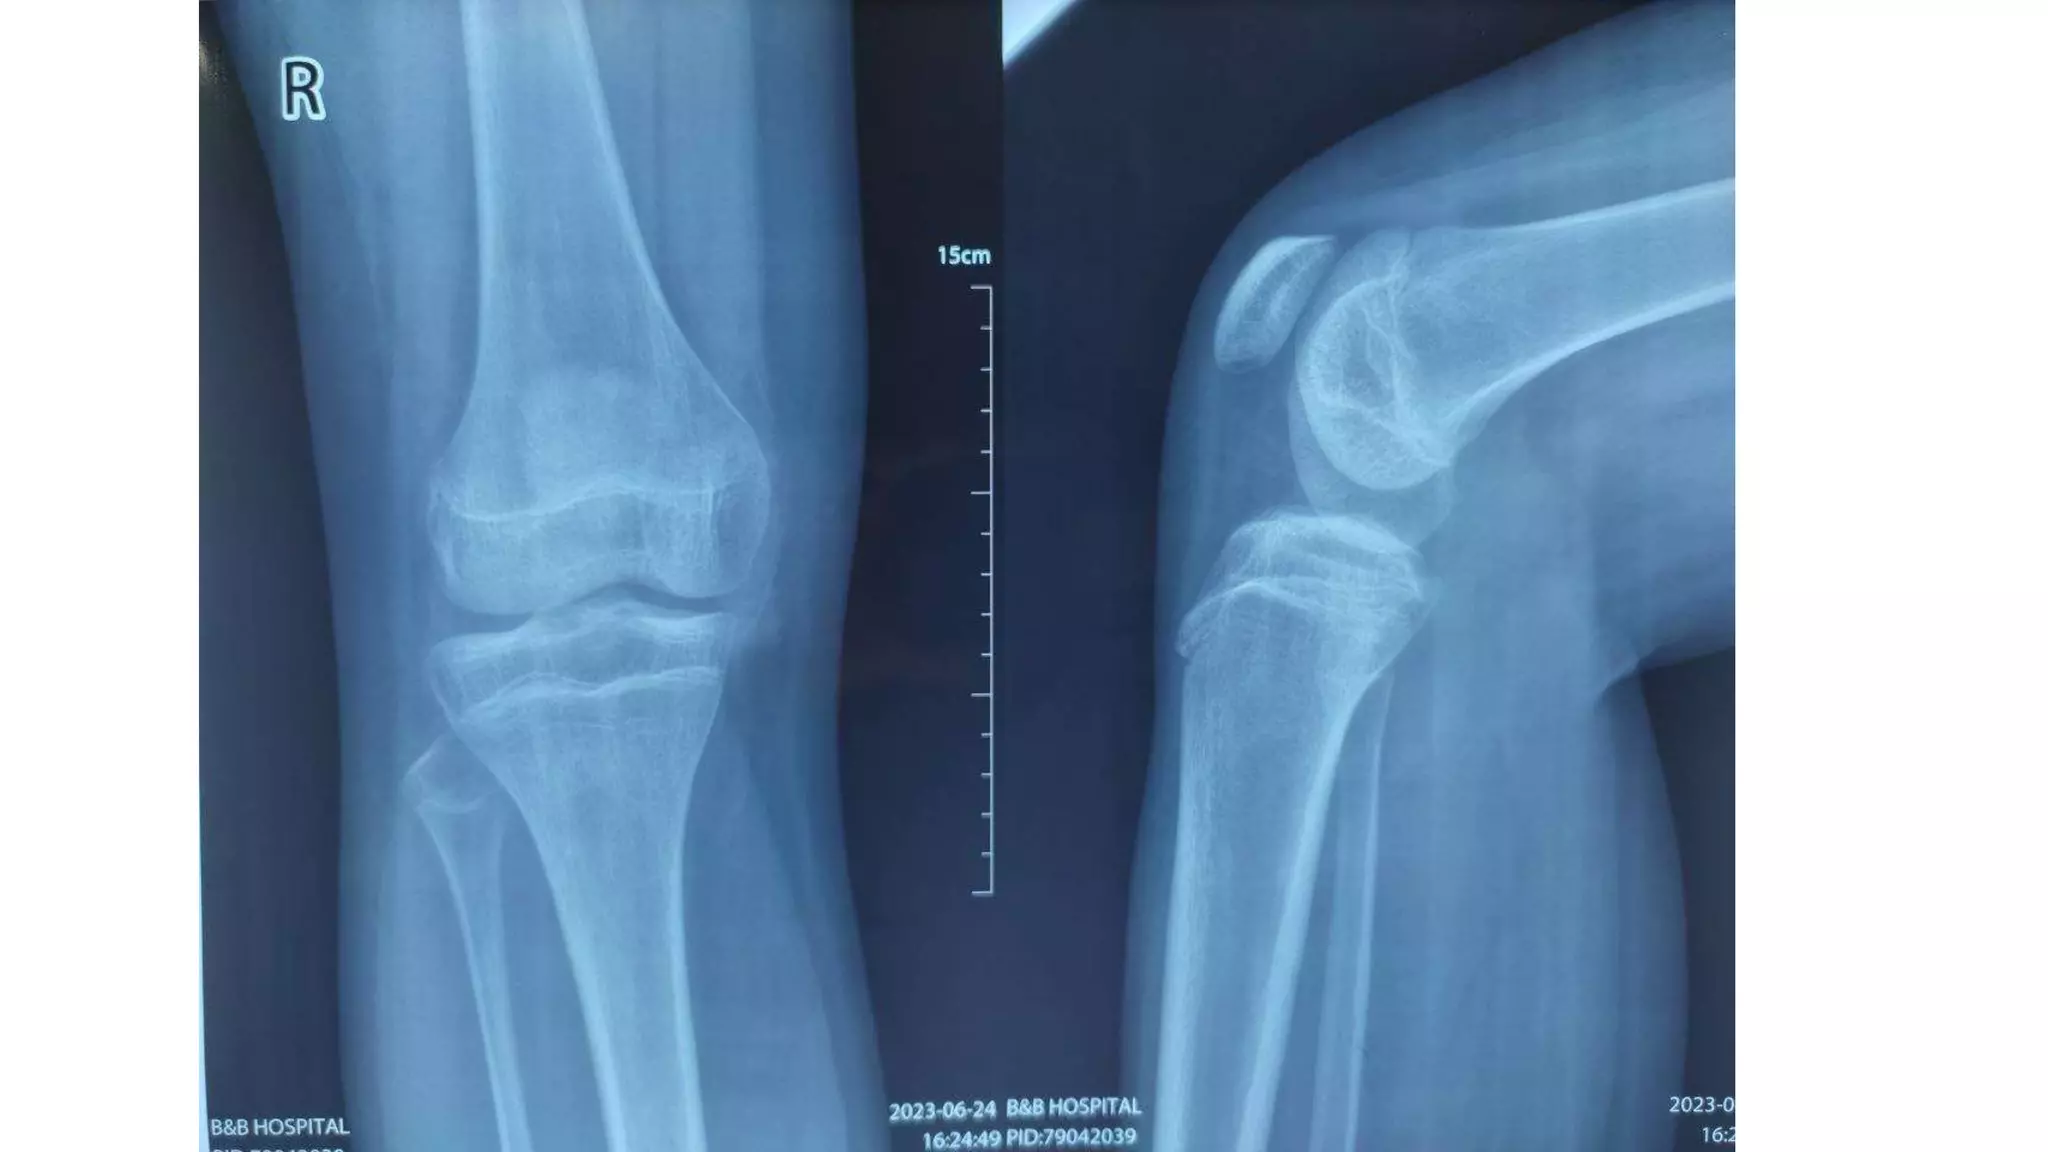

A 16-year-old boy injured his right knee while playing football when he missed a kick. His knee dislocated but reduced spontaneously. On examination, he had significant swelling and limited range of motion of his knee from 0 to 120 degrees. Tests for ligament damage were negative but the medial facet of his patella was tender.